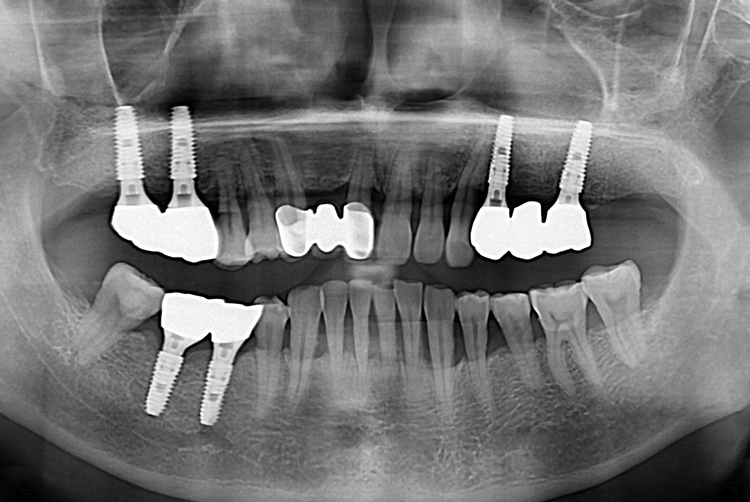

[임플란트] 어금니 임플란트

치료후 : 2019-03-26

세종치과는 많은 환자와 다양한 케이스를 바탕으로

항상 편안한 임플란트 수술을 제공하고자 노력하고,

오래동안 튼튼히 쓸 수 있는 임플란트 수술을 가장 큰 목표로 삼고 있습니다.